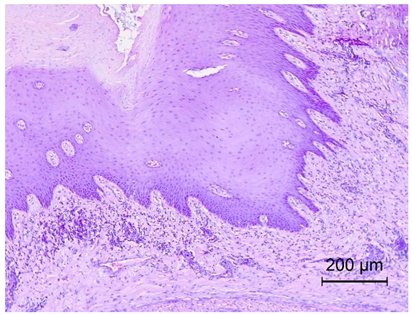

The increasing level of WBCs in the SBDS group could be caused by the protruding tongue and short beak, which are gateways for infection. These features may not only cause local issues such as keratinisation and inflammation of the tongue surface, but may also weaken the mechanical barrier, allowing pathogens to infect the respiratory system. The lungs of the SBDS ducks showed significant inflammatory infiltrates, confirming this thesis. A similar situation occurred in the intestines, where inflammation processes caused changes even in the deeper layers of the intestines. Similar histopathological lesions were observed by Hoan et al. and Soliman et al. [19,20].

The abbreviated beak leads to tongue protrusion and infections in both the respiratory and digestive tracts, as confirmed by histopathological findings. These findings reveal pronounced inflammatory infiltrates predominantly composed of neutrophils and lymphocytes, along with significant vascular congestion, particularly in the pulmonary tissues and gastrointestinal tract. The morphological abnormalities, including the abbreviated beak and protruding tongue, are linked to these pathogenic changes. This article is a valuable resource, providing detailed images and a comprehensive explanation of the disease. The phenomenon of viral-induced secondary dwarfism in veterinary contexts warrants further investigation, particularly given the unique replication pattern of this virus within osseous tissues without eliciting overt inflammatory responses in the bone tissue. This is evidenced by the markedly reduced ALT levels observed in SBDS-affected ducks compared to the healthy control group. This form of dwarfism, characterised by an abbreviated beak and associated with significant pathological changes, is unique in veterinary medicine. This article emphasises the crucial role of the virus in the development of this condition and highlights the need to establish reference ALT values for this form of dwarfism. By providing detailed images and a comprehensive explanation of the disease mechanism, this study addresses a significant gap in the diagnostic framework for veterinary care, offering valuable insights into the distinct pathogenic processes involved.

Table 4. Histopathology results of Pekin ducks with short beak and dwarfism syndrome (SBDS).

OrgansSBDS GroupNo. of Figs

LungsSevere inflammatory infiltrate forms of heterophilic and lymphocytic cells and congestion.

Exudates formation.

Applsci 14 08637 i001

TongueKeratinisation on the surface of the tongue.

Degeneration of the tongue along with ulceration.

Inflammatory infiltrate heterophilic cells.

Proliferating blood vessels around the inflammation.

Applsci 14 08637 i002